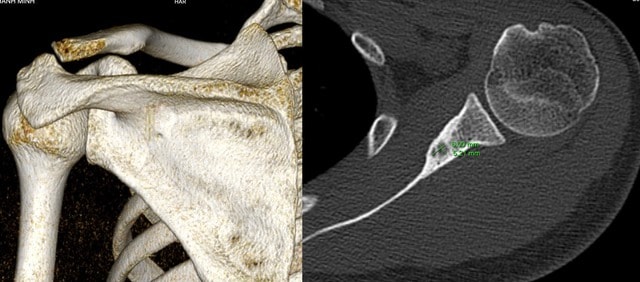

Một lần tình cờ đọc được thông tin liên quan đến tình trạng của bản thân có thể do khối u ở xương bả vai, bệnh nhân đã vào TP.HCM để chẩn đoán và điều trị. Tại đây, các bác sĩ chẩn đoán anh M có u xương dạng xương (osteoid osteoma). Phác đồ điều trị bác sĩ đưa ra là điều trị nội khoa trong một thời gian nếu không thuyên giảm thì can thiệp phẫu thuật.

“Bản thân tôi khá lo lắng tại vì hướng phẫu thuật khá phức tạp, khối u rất nhỏ (1cm) nằm ở khu vực khó tiếp cận, chưa kể nằm trọn trong xương khiến xác định chính xác vị trí khó khăn, rủi ro lớn và khả năng hồi phục lâu. Điều lo lắng nhất của tôi là việc uống thuốc giảm đau hằng ngày có khả năng gây tổn thương gan thận dạ dày tim mạch rất lớn. Mặc dù kiểm tra chức năng gan thận thường xuyên nhưng nó vẫn là một bóng ma gây ám ảnh hằng ngày đối với tôi” – bệnh nhân chia sẻ.

Trực tiếp điều trị ca bệnh, TS.BS Nguyễn Ngọc Cương (Trưởng khoa Can thiệp điện quang – Bệnh viện Đại học Y Hà Nội) cho biết: Khi đã phát hiện ra vị trí tổn thương, các bác sĩ về ngoại khoa khá “e ngại” về ca phẫu thuật này. Bởi tổn vùng xương là một ổ rất nhỏ chỉ có 5mm nằm ở trong xương vai. Trong khi đó xương vai là một xương dẹt rất khó xác định được vùng tổn thương, đây gần như là một phương án không khả thi.